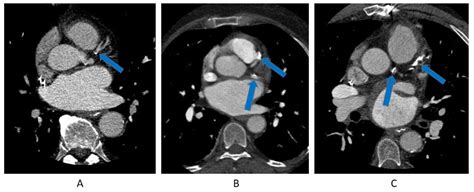

Coronary Artery Calcium scoring is a specialized type of computed tomography (CT) scan that focuses on the heart. Unlike traditional CT scans, CAC scoring specifically looks for calcium deposits in the coronary arteries. These deposits are a sign of atherosclerosis, a condition where plaque builds up in the arteries, narrowing them and increasing the risk of heart attacks and strokes.

During a CAC scan, the patient lies on a table that slides into a CT scanner. The scanner takes multiple X-ray images of the heart from different angles. A computer then processes these images to create a detailed picture of the coronary arteries. The amount of calcium in the arteries is measured and given a score, known as the Agatston score.